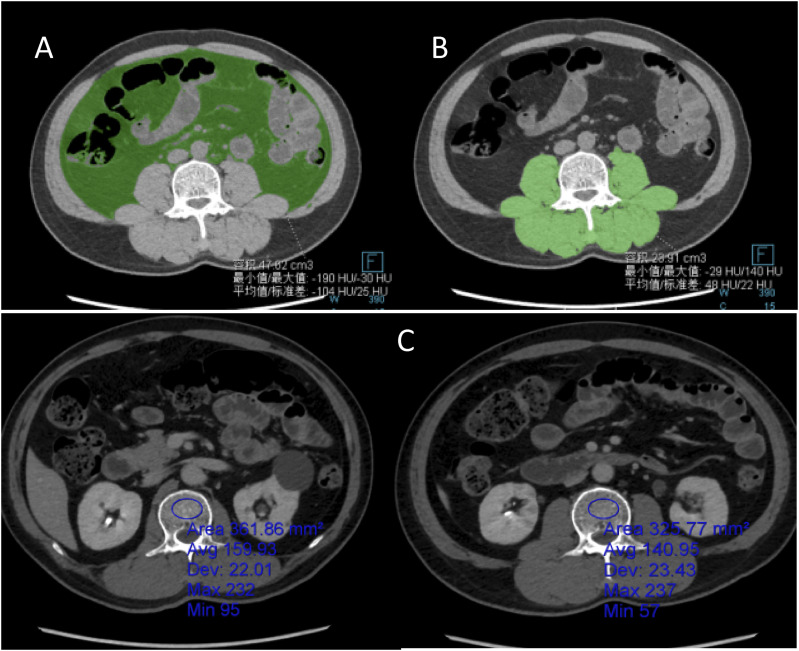

IntroductionContrast-enhanced computed tomography (CT) is the primary imaging modality for accurate risk stratification in gastrointestinal stromal tumors (GISTs). However, contrast-enhanced CT may not always be accessible or suitable for all patients undergoing risk assessment of GISTs. Therefore, this study explored the use of non-enhanced CT imaging for assessing body composition in patients with GISTs to preoperatively predict risk stratification.MethodsWe retrospectively analyzed 233 patients with GISTs who met the inclusion criteria. Pretreatment complete abdominal CT images from these patients were processed and analyzed using the Siemens Syngo imaging system. The data were subsequently organized and analyzed using the SPSS software (version 26.0).ResultsThrough two independent samples t-tests, Mann-Whitney U tests, and chi-square tests (including corrected chi-square tests and Fisher's exact tests), the intermediate-high risk group exhibited a lower visceral fat index (VFI) and higher tumor volumes and proportions of necrosis (P < .05), compared to the low-risk group (P < .05). No statistically significant differences were observed in the other indicators. Our research demonstrates that tumor volume is positively correlated with the National Institutes of Health (NIH) classification and exhibits the highest specificity among the four models (specificity = 0.735). However, its sensitivity is lower than that of the combined model (sensitivity = 0.803) and the VFI model (sensitivity = 0.972).ConclusionBased on the vascular abundance index, tumor volume, and necrosis status observed in the CT plain scan images of patients with GIST, a comprehensive predictive model was developed. This model can accurately predict the NIH grade of stromal tumors, thereby providing a robust basis for formulating effective treatment strategies and improving the prognosis of patients with GISTs who cannot undergo contrast-enhanced CT.